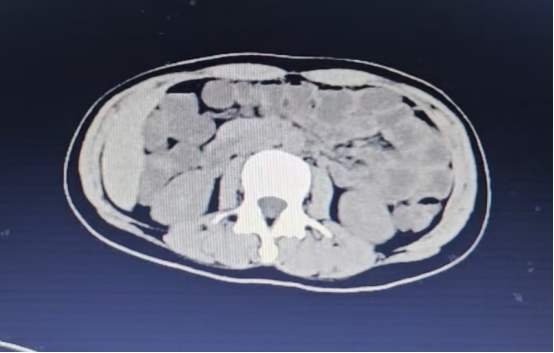

患者为26岁女性,因家庭矛盾口服草铵膦250ml,随即出现恶心、呕吐等急性中毒症状。患者呕吐物为胃内容物,症状逐渐加重,且意识逐渐模糊。在当地医院接受初步治疗,由于病情危重,被紧急转至遵医附院急诊科。入院时,患者神志呈嗜睡状。腹部CT检查显示,患者腹腔内肠管出现多发性积气和积液,液气平面明显。考虑到患者病情危急,急诊医护团队立即启动紧急救治措施,进行毒物清除和支持性治疗。

腹腔多发肠管积气积液